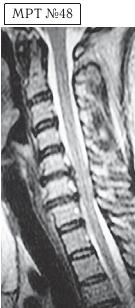

На МРТ № 47 наблюдается сглаженность лордоза с незначительной кифотизацией, которая привела к абсолютному стенозу спинномозгового канала и блоку ликворных путей, а также протрузии в сегменте СIV-СV, вентральному спондилёзу в сегменте CV-CVI и остеофитозу в сегменте CVI-CVII, гипертрофии передней и задней продольных связок. Это наиболее значительные проблемы в данном отделе. ![]() На МРТ № 48 наблюдается сглаженность лордоза, но без кифотической деформации, снижение высоты межпозвонковых дисков, протрузии в сегментах CV-CVI и CVI-CVII, частично компенсированные спондилёзом, выражены краевые остеофиты на данном уровне, абсолютный стеноз и блок ликворных путей, гипертрофия передней и задней продольных связок. ![]() На МРТ № 49 наблюдается кифоз шейного отдела позвоночника, хотя он и не привёл к абсолютному стенозу спинномозгового канала позвоночника, однако значительно нарушил ликвородинамику. Вентральное эпидуральное пространство блокировано вершиной кифоза с экскавацией и оттеснением спинного мозга, а дорсальное эпидуральное пространство блокируется чуть ниже от вершины задней стенкой спинномозгового канала. МРТ № 50